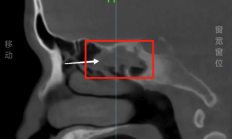

9月9日消息,据媒体报道,阿杰(化名)18年来饱受鼻塞、流脓涕的困扰,一直以为是感冒或过敏,直到今年7月到深圳大学总医院检查,才揭开真相。医生凭借经验,跳过鼻内镜直接建议CT检查,结果发现他的右侧蝶窦存在占位性病变,初步怀疑是“骨瘤”,同时...